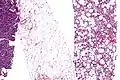

Histopathology of liposarcomas

Fig. 3 Lower-power micrograph of myxoid liposarcoma tumor -

Fig. 4 Higher-power micrograph of myxoid liposarcoma tumor

Pathology

Histopathologic analyses of MLS (see Figs. 3 and 4 in the below Histopathology of liposarcomas section) reveals cells scattered throughout a myxoid matrix (i.e. a connective tissue background that appears more blue or purple than the red color of normal connective tissue when these tissues are properly prepared, H&E stained, and viewed microscopically). These cells are lipoblasts, some of which are signet ring-shaped (a shape suggesting that the cell may be neoplastic), oval-shaped, or round-shaped.[40] MLS tumors may be hypercellular and contain solid sheets of round cells that comprise at least 5% of all cells or low cellularity populated with cells that have bland nuclei and <5% round cells in a background of curving capillaries resembling a chicken-wire pattern. Tumors that contain at least 5% round cells are classified as high-grade while those with <5% round cells are classified as low-grade.[39] High-grade MLS tumors typically take a more aggressive clinical course than low-grade MLS tumors.[40]